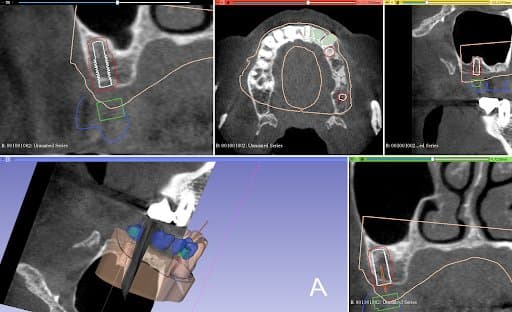

Planning of implant placement based on the CBCT

After the healing phase, a CBCT was taken to plan the implant placement and surgical technique. Due to the poor remaining bone volume and quality, it was decided to place the implants using a surgical guide to guarantee their accurate position in the areas where the bone quality was sufficient. Bone augmentation was discarded as a solution due to the complexity of this procedure for this specific clinical case. Alginate impressions were taken of both arches and sent to the dental laboratory, alongside the instructions for the implant positions, for design and fabrication of the surgical guide . A professional tooth cleaning was performed to prepare the oral cavity in a good hygienic condition for the operation.

Design Stage:

The plaster models were made from the impressions and digitized in Mr. Neubarth´s laboratory using a desktop scanner (Sirona InEos X5). The digital models could be superimposed with the CBCT (3D Accuitomo 170) in the software (Blender for dental). Artificial teeth were set up in the software and two implants of the appropriate length and diameter (Twinfit from Dentaurum) were imported.